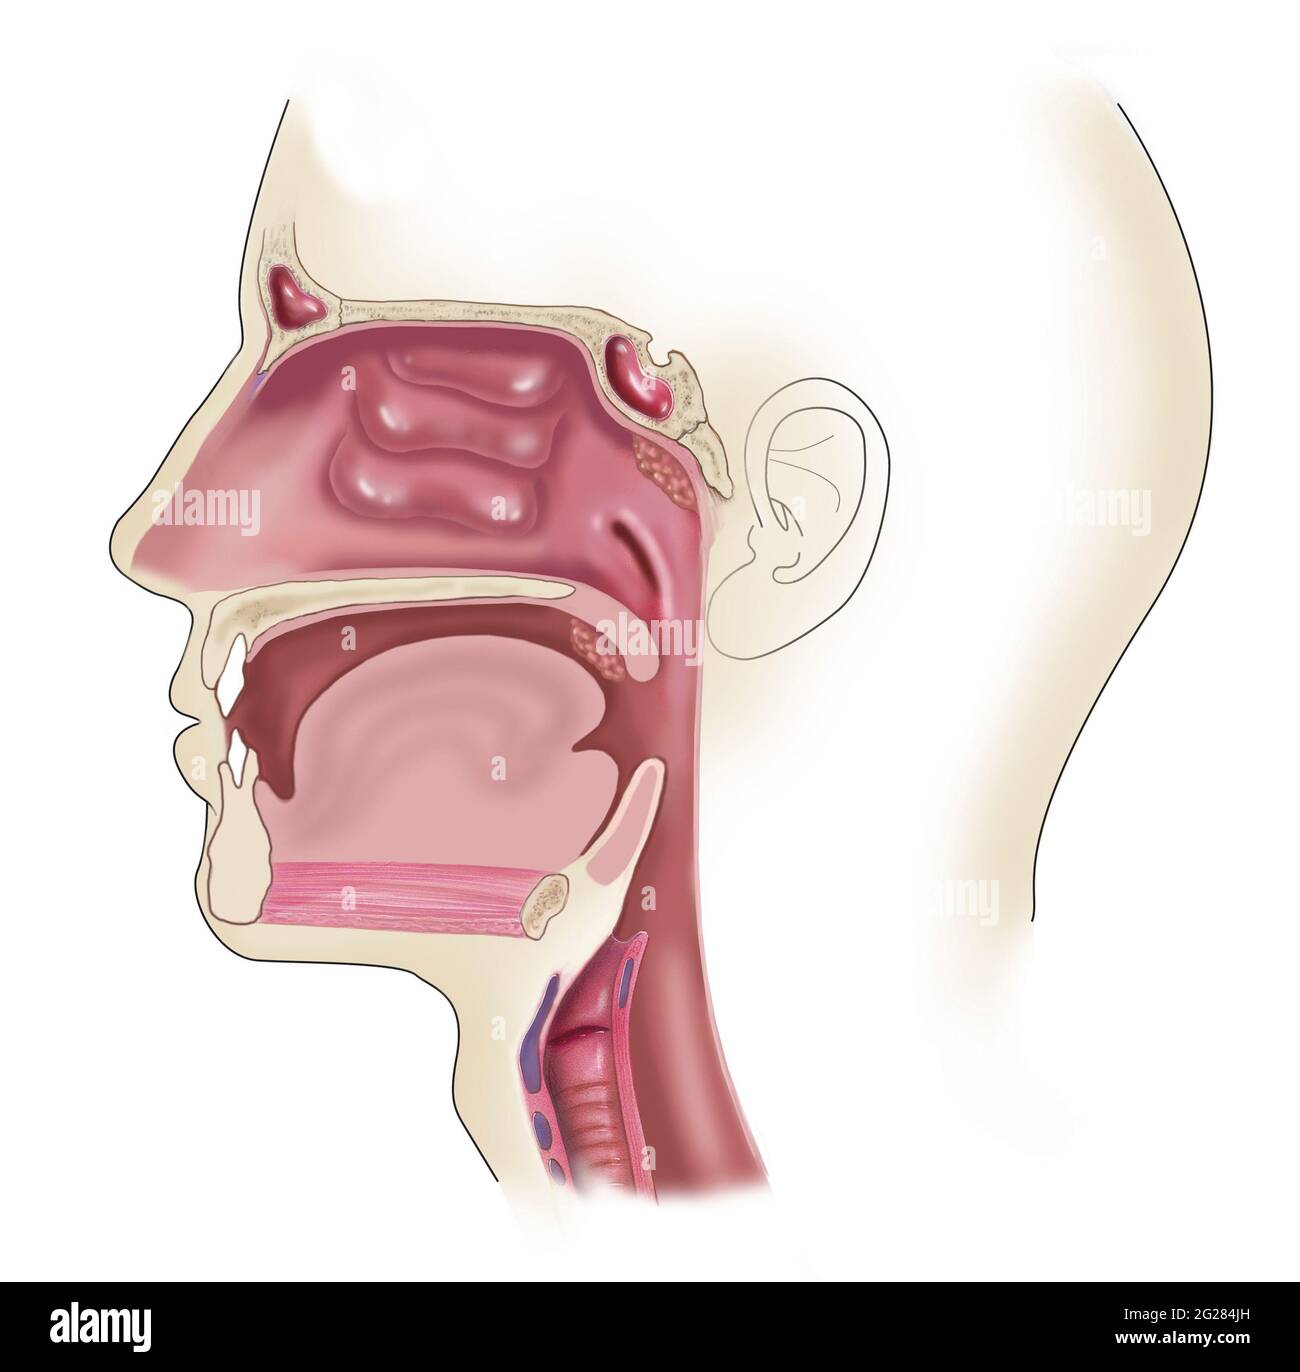

Seitenansicht des Kopfes, wo sich geschwollene und vergrößerte Mandeln befinden. Stockfotohttps://www.alamy.de/image-license-details/?v=1https://www.alamy.de/seitenansicht-des-kopfes-wo-sich-geschwollene-und-vergrosserte-mandeln-befinden-image431667785.html

Seitenansicht des Kopfes, wo sich geschwollene und vergrößerte Mandeln befinden. Stockfotohttps://www.alamy.de/image-license-details/?v=1https://www.alamy.de/seitenansicht-des-kopfes-wo-sich-geschwollene-und-vergrosserte-mandeln-befinden-image431667785.htmlRF2G284JH–Seitenansicht des Kopfes, wo sich geschwollene und vergrößerte Mandeln befinden.

Seitenansicht des Kopfes, wo sich geschwollene und vergrößerte Mandeln befinden. Stockfotohttps://www.alamy.de/image-license-details/?v=1https://www.alamy.de/seitenansicht-des-kopfes-wo-sich-geschwollene-und-vergrosserte-mandeln-befinden-image431668088.html

Seitenansicht des Kopfes, wo sich geschwollene und vergrößerte Mandeln befinden. Stockfotohttps://www.alamy.de/image-license-details/?v=1https://www.alamy.de/seitenansicht-des-kopfes-wo-sich-geschwollene-und-vergrosserte-mandeln-befinden-image431668088.htmlRM2G2851C–Seitenansicht des Kopfes, wo sich geschwollene und vergrößerte Mandeln befinden.